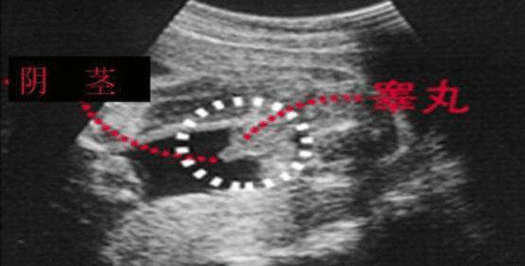

四维彩超怎么看男女 教你另辟蹊径看胎儿性别